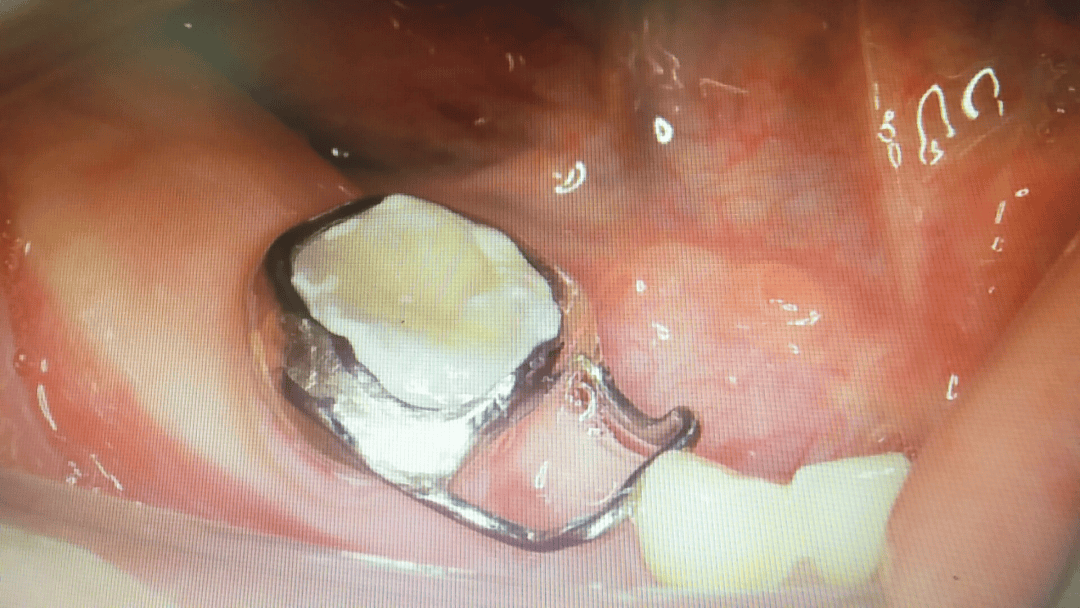

一般乳牙缺失时,医生可以帮孩子做一个间隙保持器,保持空间,等待恒牙萌出。

间隙保持器

年轻恒牙缺失,则可以进行活动义齿修复,满足孩子的美观及咀嚼、发音需要。因为儿童颌骨不断发育增长,牙弓逐渐扩大,因此一般一到两年就要更换义齿,等成年后可选择种植牙等修复方式。